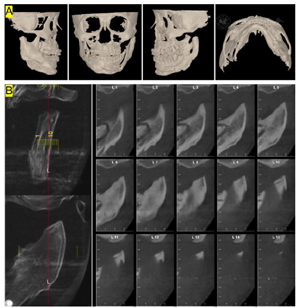

治疗前CBCT检查(图6):左侧髁突膨大,突出关节窝内,骨质密度降低

本病例患者在此次求治3年前曾于外院行"左侧MEDPOR假体植入+颏成形术",以期通过改变下颌体部形态并摆正颏部获得美观改善。此种方法创伤虽小,但并未针对病因治疗,因而无法阻止髁突增生活跃期带来的疾病进行性加重。临床工作中双侧髁突骨盐代谢比作是评价髁突增生程度的客观指标,以患侧代谢超过对侧的17%作为判断是否切除患侧髁突的标准。本病例中该指标为1:1.76,远远大于17%的标准,代表患侧髁突增生活跃。从CBCT来看,髁头及髁颈部可见囊性变区域,为增生代谢活跃导致。